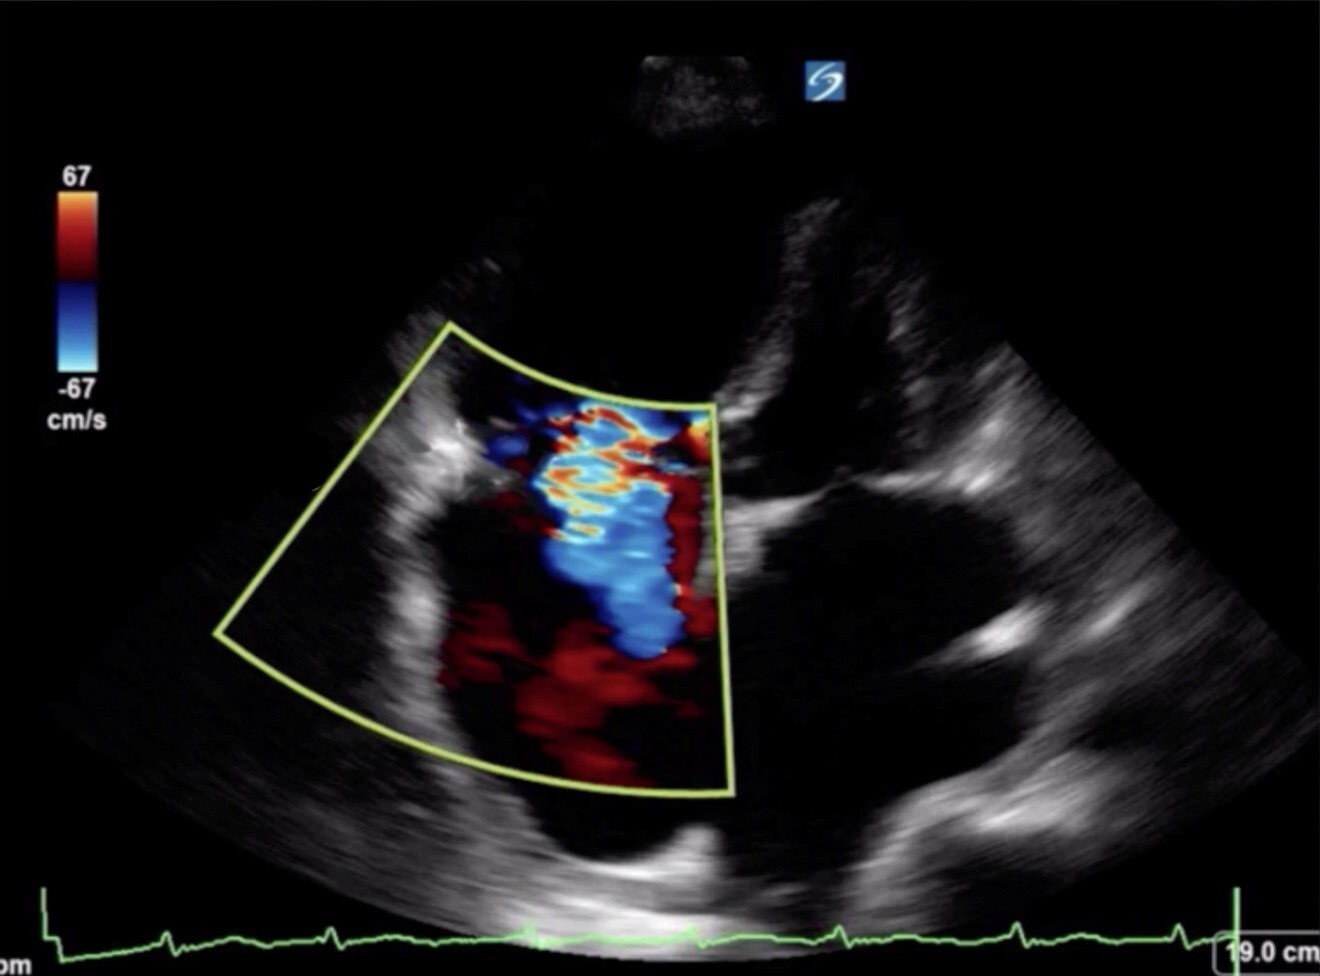

Cardiac 2 Tricuspid Regurgitation for RVSP Image